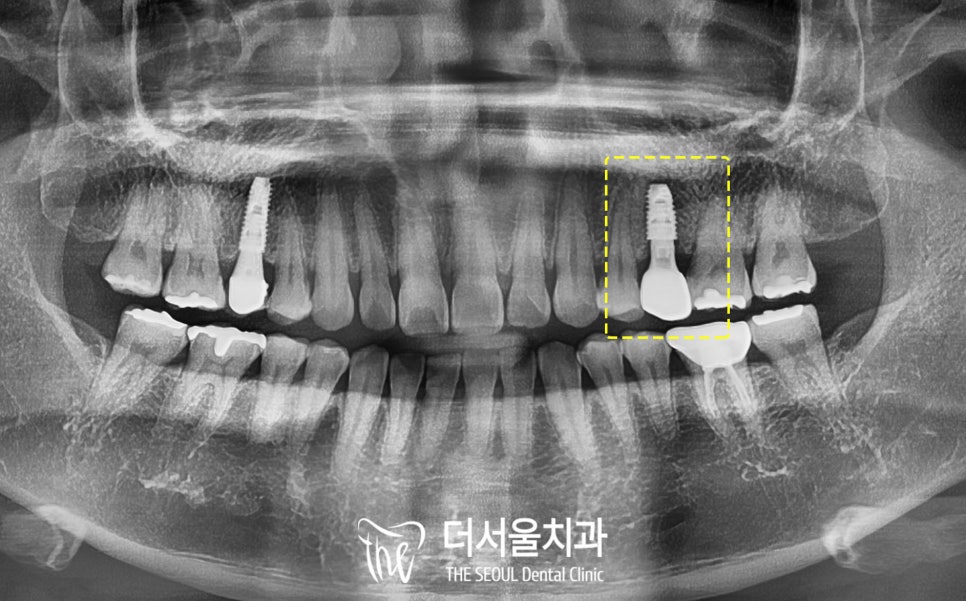

부러진 치근을 뽑고

그 자리에 정확하게

픽스처를 심었는데요,

저작력을 잘 버틸 수 있도록

치조골이 튼튼한 곳에

알맞게 식립을 진행해 드렸습니다.

잇몸뼈의 너무 바깥쪽도 아니고

너무 안쪽도 아닌 중앙에 잘 위치 시켰으며

양쪽 치아와의 간격도

잘 맞춰서 심어진게 보이시죠?

2개월 반 만에 고정력도

충분히 확보되었습니다.

그래서 맞춤형 어버트먼트를 제작하고

보철을 올릴 준비까지 되었습니다.

이 환자의 경우

예전에 다른 곳에서 한(이제는 사라져버린..)

오른쪽 위 작은 어금니 임플란트는

방향도 조금 기울어져 있어서

지속적인 관리가 필요한데

심지어 보철에 홀이 없는 타입이라

a/s가 힘듭니다.